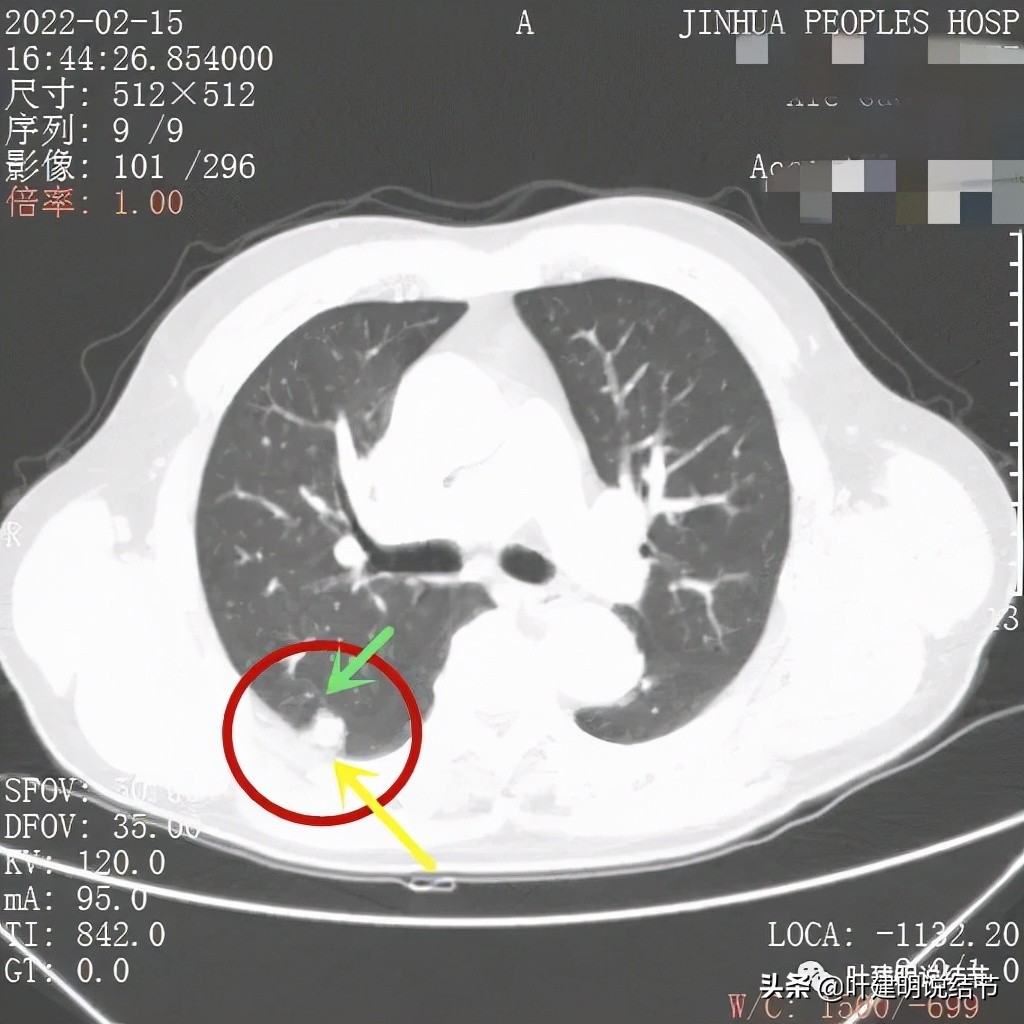

边缘似见少许磨玻璃成分(绿色箭头),病灶与胸壁间离的这么近,但有低密度分界(黄色箭头),说明不是普通炎症性,如果炎症会有水肿,间隙一般不清

上图除了间隙以外,病灶有的地方有膨胀性,往外鼓出去一点(砖色箭头)

膨胀性以及与胸壁间隙

上图示病灶边缘毛糙(紫色箭头),以及与胸壁间的间隙存在(黄色箭头)